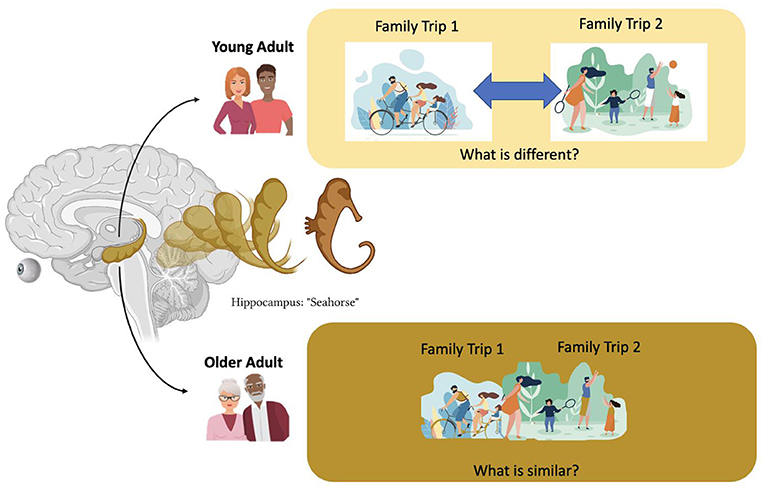

The rise of the ‘emotional brain’

As we age, the risk-taking element of our brain starts to fade, and we are less controlled by the dictates of our hormones — and a more sophisticated mental acuity replaces this.

- 根据文章,为什么年长者会在晚年表现得更聪明睿智?